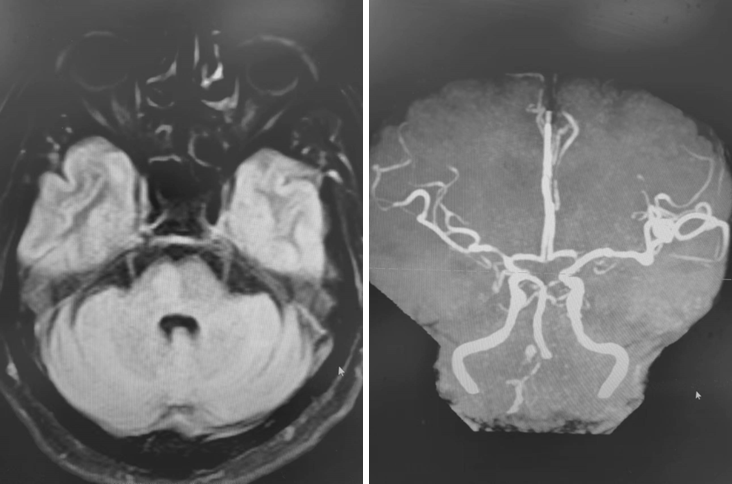

首次发病:

DWI

MRA

重要影像结论:后循环供血区多发梗死灶,后循环血管显影不良。